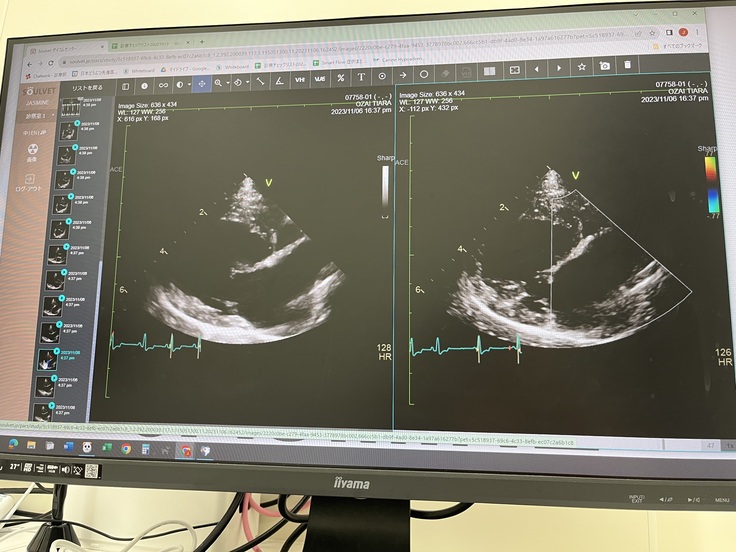

2023.11.6

手術を決心し

お願いする循環器専門病院にて

術前検査。

心肥大や肺の状態などを診て頂き

総合的な判断で

今が手術を受けるタイミングで良さそう

との事でした。

※僧帽弁閉鎖不全症とは

高齢の犬で最も多く認められる心疾患です。

心臓は右心房、右心室、左心房、左心室の

4つの部屋に分かれています。

僧帽弁とは、左側の左心房と左心室の

間にある弁のことです。

通常は、僧帽弁の働きにより

左心房から左心室への一方向にしか

血液は流れませんが

僧帽弁閉鎖不全症では

弁がうまく閉まらなくなることで

逆方向の血流が認められるようになります。